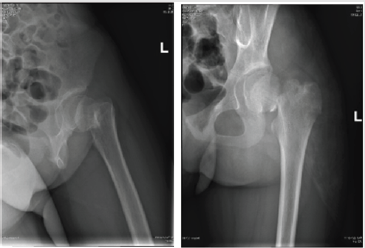

The patient is a 11-year-old girl. In August 2019, she sustained an injury on her left hip, she fell down from a chair at home. The subsequent X-ray showed a femoral neck fracture in her left hip (Delbet II), totally displaced. She came to our hospital three days after the injury. The X-ray and CT scans confirmed the total displacement of the fracture, no osteoepiphysis involved (Figure 1). In the preoperative discussion, we made the therapy project that we would manage the fracture by internal fixation after reducing the fracture anatomically. Which kind of internal fixation would be adopted remained controversial? K-wires do not have compressive effect on fracture ends. Cannulated screws cannot provide enough stabilization because of the limited length. Locking compression paediatric hip plate may results in longer operation time and more blood loss compared with cannulated screws and K-wires. So, we decided to adopt both K-wires and cannulated screws, in order to avoid the defects. After necessary preoperative preparation, we proceeded with reconstructive surgery. Under general anesthesia, we first made close reduction with the use of traction table and got a mostly satisfactory result. Then we put a K-wire into the femoral head and achieved anatomical reduction by stirring the K-wire.